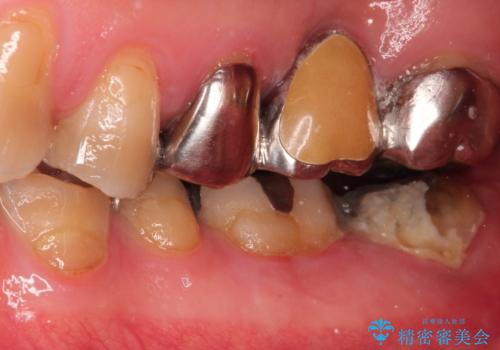

【ヘミセクション】なんとか残したい、割れた奥歯。

- 他院で、抜歯してインプラントだと診断され、セカンドオピニオンで来院されました。

近心根が垂直破折しており保存不可能で抜歯適応だと判断しましたが、できることなら少しでも保存したいとの希望があり、今後のリスクを説明した上で遠心根を保存する意思決定を行いました。

今回の症例は遠心根を保存するメリット・デメリットを患者さんと話し合い、治療を進めております。

条件が少しでもよくなる様に、再生治療および確定外科を行い良好な歯周状態でオールセラミッククラウンを装着しております。